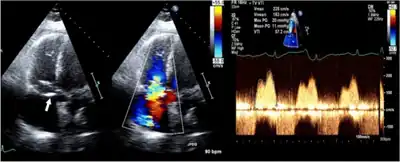

Tests include chest X-ray and ECG.[2] Diagnosis is confirmed by an echocardiograph, which will also allow the physician to assess its severity.[2]